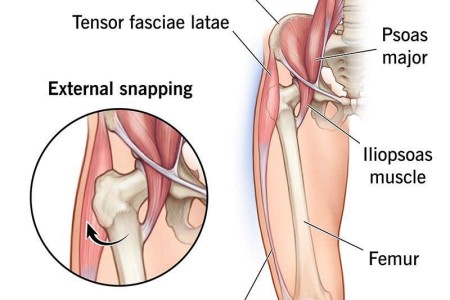

Snapping Hip Syndrome